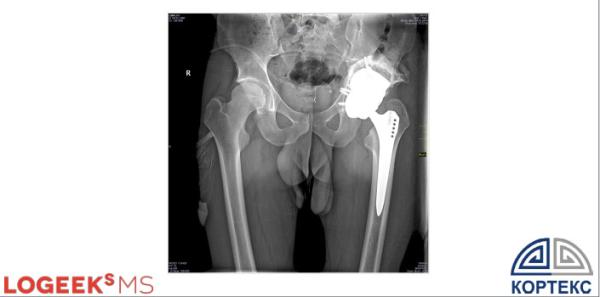

Первичное и ревизионное эндопротезирование тазобедренного сустава — важно определить показания к использованию индивидуального имплантата.

Использование пластиковых 3D-моделей в ревизионном эндопротезирование ТБС

Ревизионное эндопротезирование ТБС с использованием индивидуальных имплантатов

Результат установки